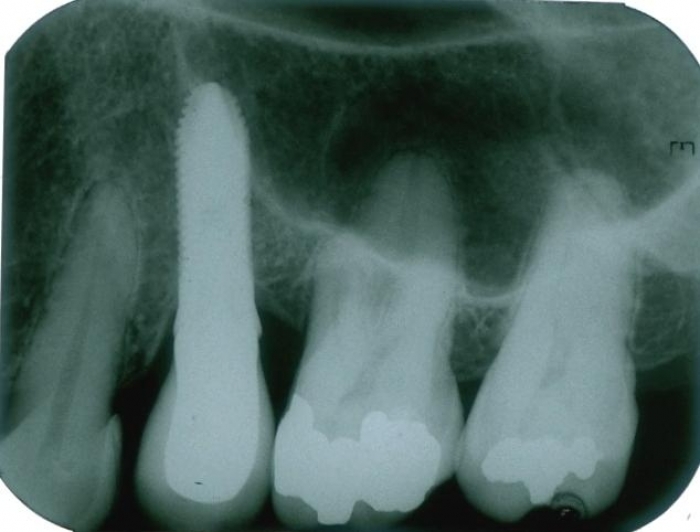

Raio X com prótese fixa em porcelana instalada sobre o implante

Raio X de 9 meses de controle